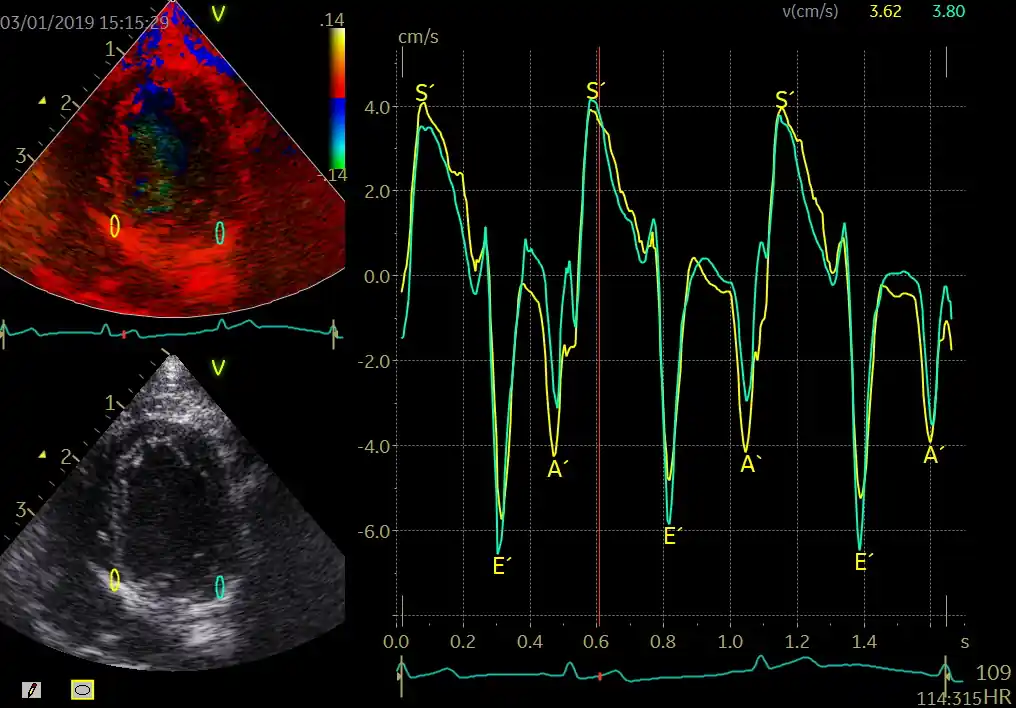

یکی از شاخصهای مهم در TDI، سرعتی به نام E′ (ایپرایم) است که نشان میدهد قلب چقدر خوب شل میشود. اگر E′ پایین باشد، یعنی قلب برای پرشدن خون به مشکل خورده است. شاخص مهم دیگر S′ (اسپرایم) است که قدرت انقباض قلب را نشان میدهد. این دو عدد ساده میتوانند اطلاعات بسیار مهمی دربارهٔ سلامت قلب ارائه دهند.

- ‘S (اسپرایم): قدرت انقباض قلب

- ‘E (ایپرایم): کیفیت شلشدن قلب

- ‘A (ایپرایم انتهایی): نقش دهلیز در پرشدن قلب

یکی از مهمترین نقاط اندازهگیری در TDI، حلقهٔ دریچهٔ میترال در نواحی Lateral (لترال , جانبی) و Septal (سپتال , دیوارهٔ بینبطنی) است. سرعتهای ثبتشده در این نواحی معمولاً با نمادهای ‘S (سرعت سیستولیک)، ‘E (سرعت دیاستولیک اولیه) و ‘A (سرعت دیاستولیک انتهایی یا ناشی از انقباض دهلیز) گزارش میشوند. این سه موج اطلاعات ارزشمندی دربارهٔ عملکرد طولی بطن چپ ارائه میدهند.

اکوکاردیوگرافی TDI (Tissue Doppler Imaging , تصویربرداری داپلر بافتی) سه موج اصلی تولید میکند که هرکدام بازتابی از یک مرحلهٔ چرخهٔ قلبی هستند: S′، E′ و A′. این امواج از حلقهٔ میترال (Mitral Annulus , حلقهٔ دریچهٔ میترال) یا حلقهٔ تریکوسپید (Tricuspid Annulus , حلقهٔ دریچهٔ سهلتی) ثبت میشوند و هرکدام اطلاعات ارزشمندی دربارهٔ عملکرد سیستولیک و دیاستولیک قلب ارائه میدهند. در این فصل، ماهیت هر موج، فیزیولوژی پشت آن، عوامل مؤثر بر تغییرات آن و کاربردهای بالینی آنها بررسی میشود.

موج ‘S (S-prime , سرعت سیستولیک بافتی) بازتابدهندهٔ حرکت طولی قلب در مرحلهٔ سیستول است. در این مرحله، حلقهٔ میترال و تریکوسپید به سمت اپکس (Apex , نوک قلب) حرکت میکنند. دامنهٔ موج S′ نشاندهندهٔ قدرت انقباض طولی میوکارد (Myocardium , عضلهٔ قلب) است. کاهش S′ میتواند نشانهٔ اولیهٔ اختلال عملکرد سیستولیک باشد، حتی زمانی که EF (Ejection Fraction , کسر جهشی) هنوز طبیعی است. این ویژگی باعث شده S′ به شاخصی حساس برای تشخیص زودهنگام کاردیومیوپاتیها، سمیت قلبی ناشی از شیمیدرمانی (Chemotherapy , درمان دارویی سرطان) و اختلال عملکرد بطن راست تبدیل شود.

موج ‘E (E-prime , سرعت دیاستولیک اولیهٔ بافتی) نشاندهندهٔ سرعت بازگشت حلقهٔ میترال به سمت دهلیز چپ در فاز پرشدگی سریع دیاستول است. این موج یکی از مهمترین شاخصهای عملکرد دیاستولیک است، زیرا مستقیماً تحت تأثیر شلشدن (Relaxation , ریلکسیشن) میوکارد قرار دارد. کاهش ‘E معمولاً اولین علامت اختلال عملکرد دیاستولیک است و در تشخیص HFpEF (Heart Failure with Preserved EF , نارسایی قلبی با EF حفظشده) نقش کلیدی دارد. برخلاف موج E داپلر جریان خون، موج ‘E کمتر تحت تأثیر پیشبار (Preload , حجم خون ورودی) قرار میگیرد و بنابراین شاخص قابلاعتمادتری برای ارزیابی ریلکسیشن است.

موج ‘A (A-prime , سرعت دیاستولیک انتهایی) بازتابدهندهٔ حرکت حلقهٔ میترال در پاسخ به انقباض دهلیز چپ است. این موج در مرحلهٔ Atrial Contraction (انقباض دهلیزی) ایجاد میشود و اطلاعاتی دربارهٔ تعامل دهلیز و بطن ارائه میدهد. افزایش A′ معمولاً در شرایطی دیده میشود که بطن سفتتر شده و برای پرشدگی نیاز بیشتری به انقباض دهلیز دارد، مانند هیپرتروفی بطن چپ (LVH , ضخیمشدن بطن چپ). در مقابل، کاهش A′ میتواند نشانهٔ اختلال عملکرد دهلیز یا آریتمیهایی مانند فیبریلاسیون دهلیزی باشد.

تفاوت بین نواحی Lateral (لترال , جانبی) و Septal (سپتال , دیوارهٔ بینبطنی) در امواج TDI اهمیت زیادی دارد. سرعتهای لترال معمولاً بیشتر از سپتال هستند، زیرا دیوارهٔ لترال متحرکتر است. در مقابل، سرعت سپتال ممکن است تحت تأثیر حرکت بطن راست قرار گیرد. بنابراین هنگام تفسیر ‘E یا ‘S باید به این تفاوتها توجه شود. در بسیاری از راهنماها توصیه میشود برای محاسبهٔ E/E′ از میانگین E′ لترال و سپتال استفاده شود تا دقت افزایش یابد.